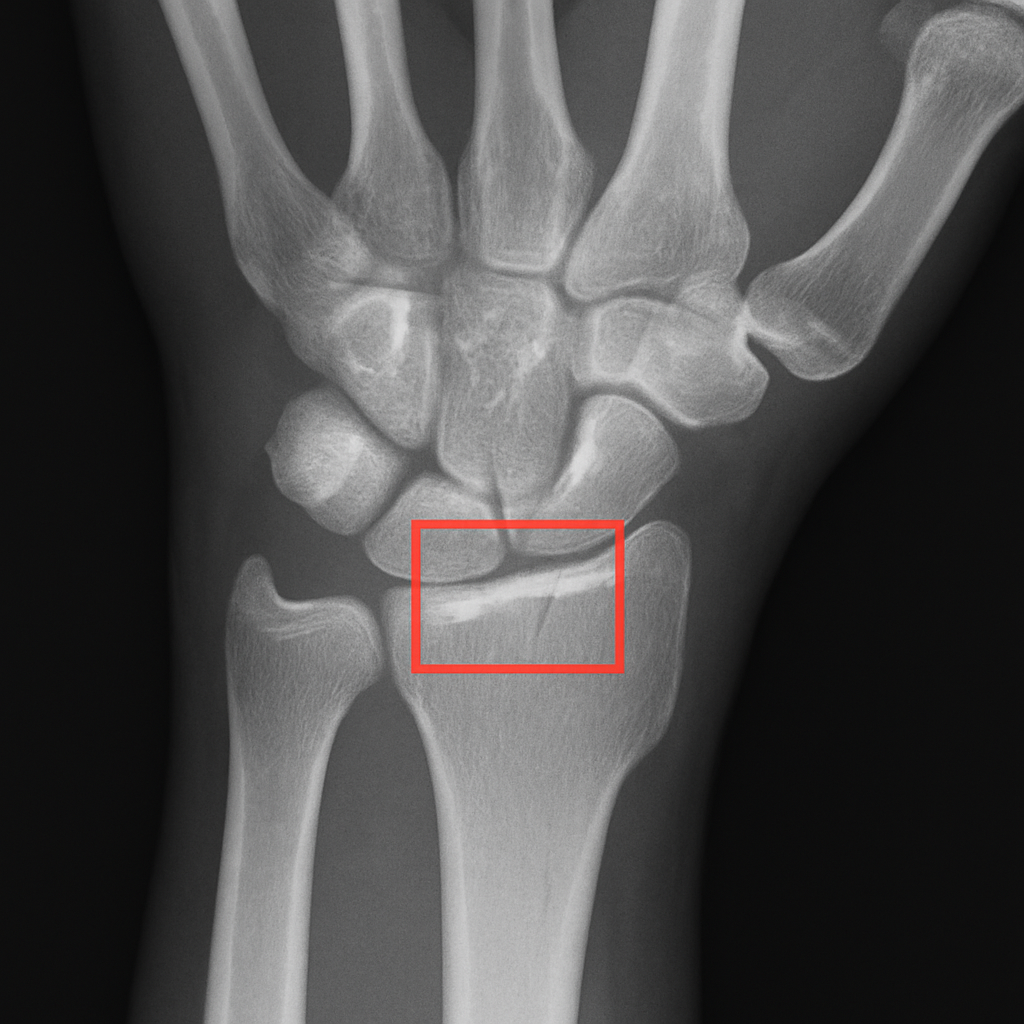

Finding the Needle in a Haystack: How AI Spots Tiny Fractures

There are many X-rays from a single examination, and finding a very small crack in all these dozens of X-rays may be difficult. Additionally, radiologists must view many images each day, creating a large backlog of exams that prevents them from quickly determining whether a bone is fractured. Therefore, having two sets of very fast “eyes” should greatly improve this problem.

In addition to providing a second set of “eyes,” AI will also greatly assist in identifying fractures and preventing medical imaging errors by rapidly reviewing a patient’s X-ray or CT scan within seconds, then sending the case directly to the radiologist if AI indicates possible fracture indicators. This is essentially allowing the radiologist to evaluate only the potentially serious cases, while the less serious cases will be evaluated later.

Another way that AI can assist in rapid and accurate fracture diagnosis is by being able to recognize patterns of injury that cannot be seen by human “eyes.” While this technology offers great promise in assisting in the recognition of the beginning stages of a fractured bone, its application in detecting early cancer may offer an even greater benefit. For example, instead of viewing an X-ray to search for a small crack in an individual’s bones, AI could use pattern recognition to identify the earliest signs of disease in an X-ray. The implications of such applications will undoubtedly have significant benefits to patients.”